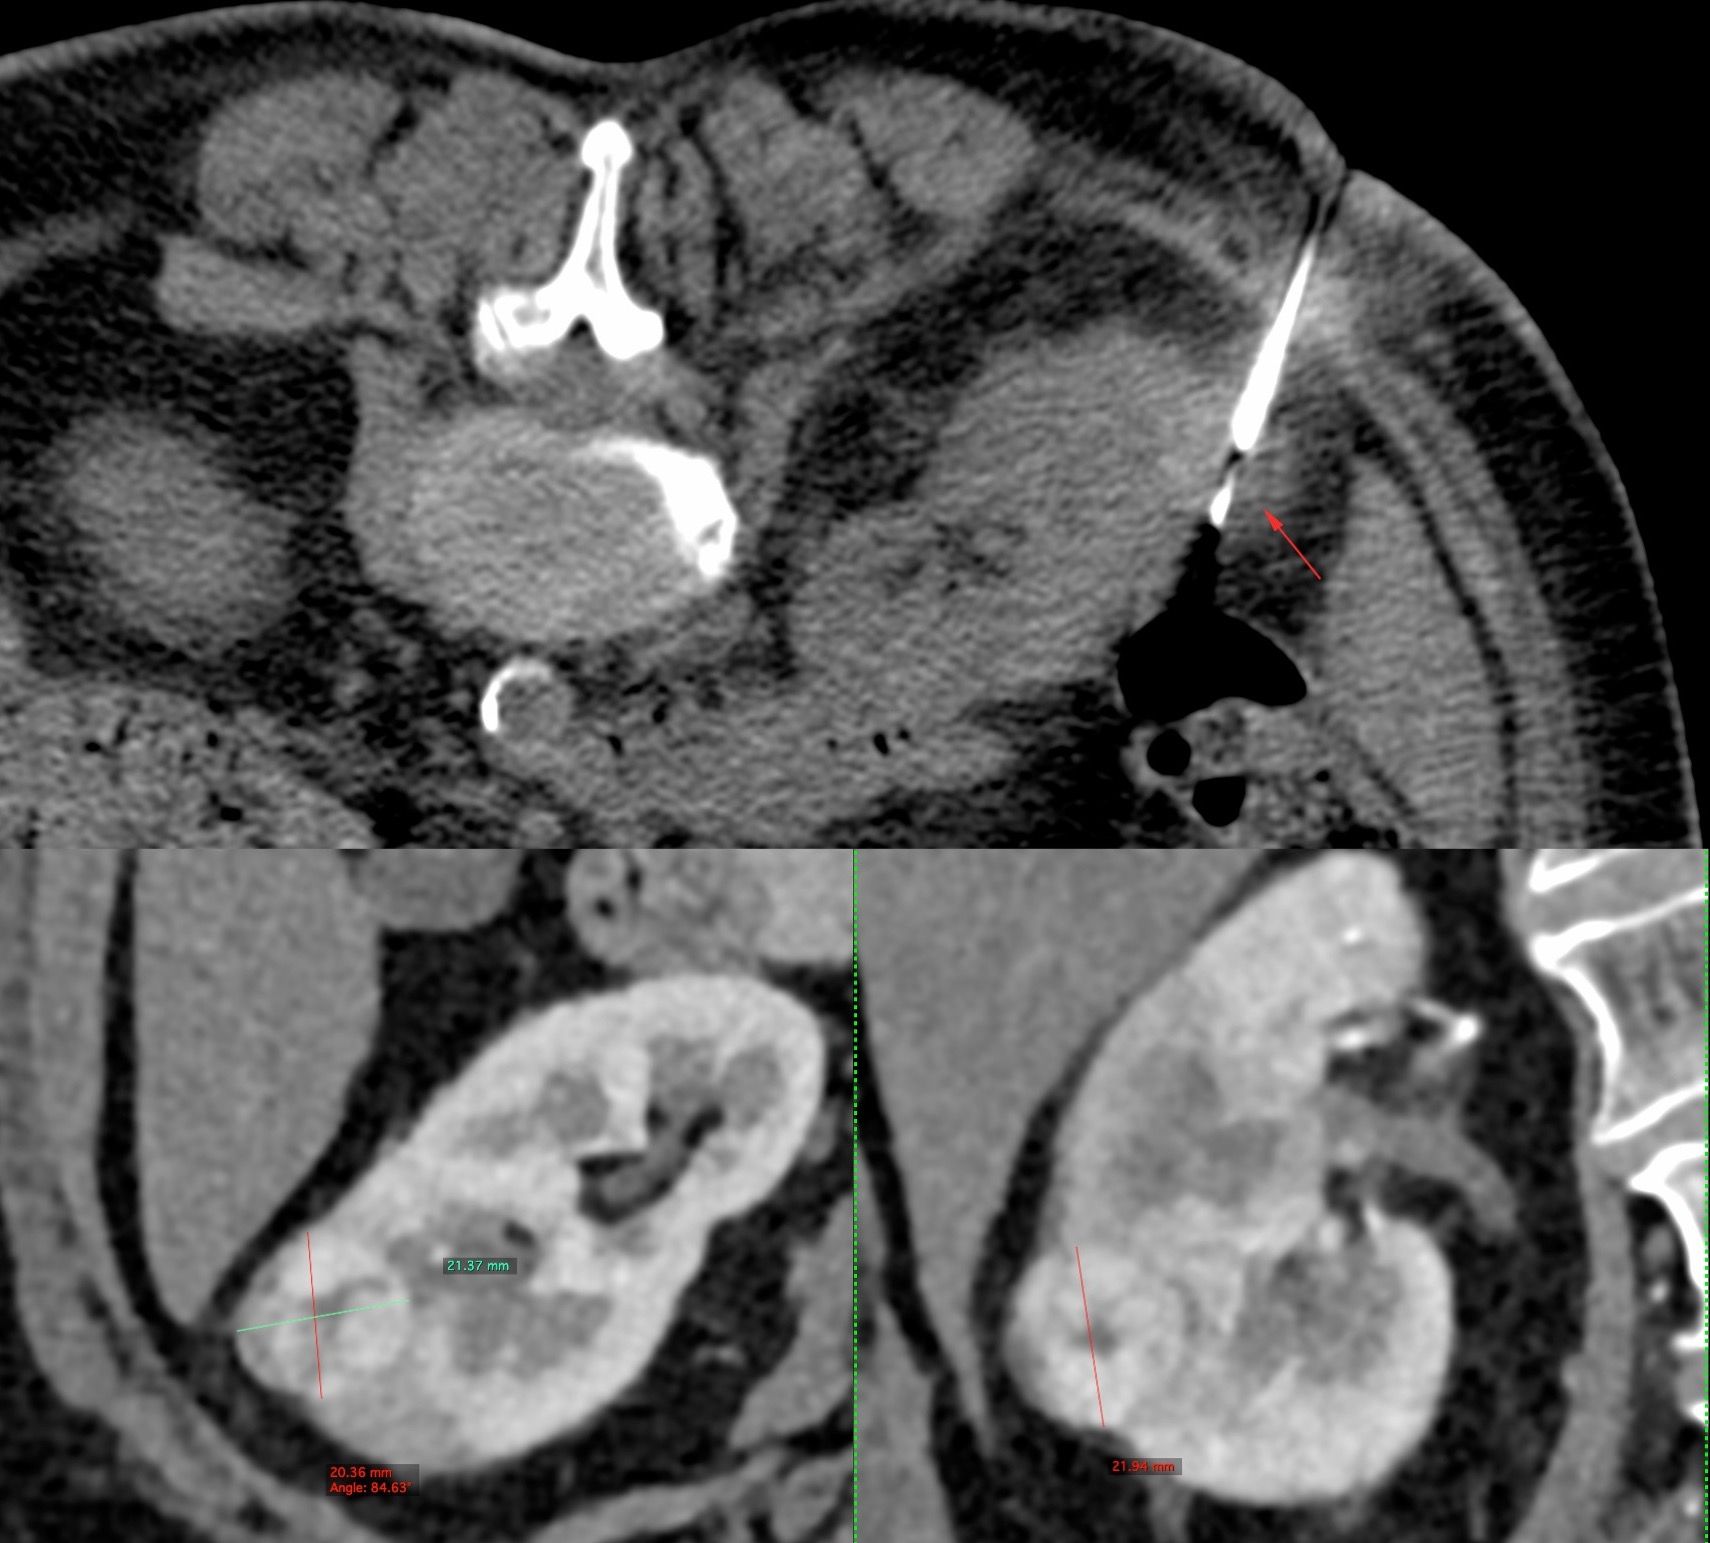

Case 20: 2.1 cm Renal Mass Biopsy